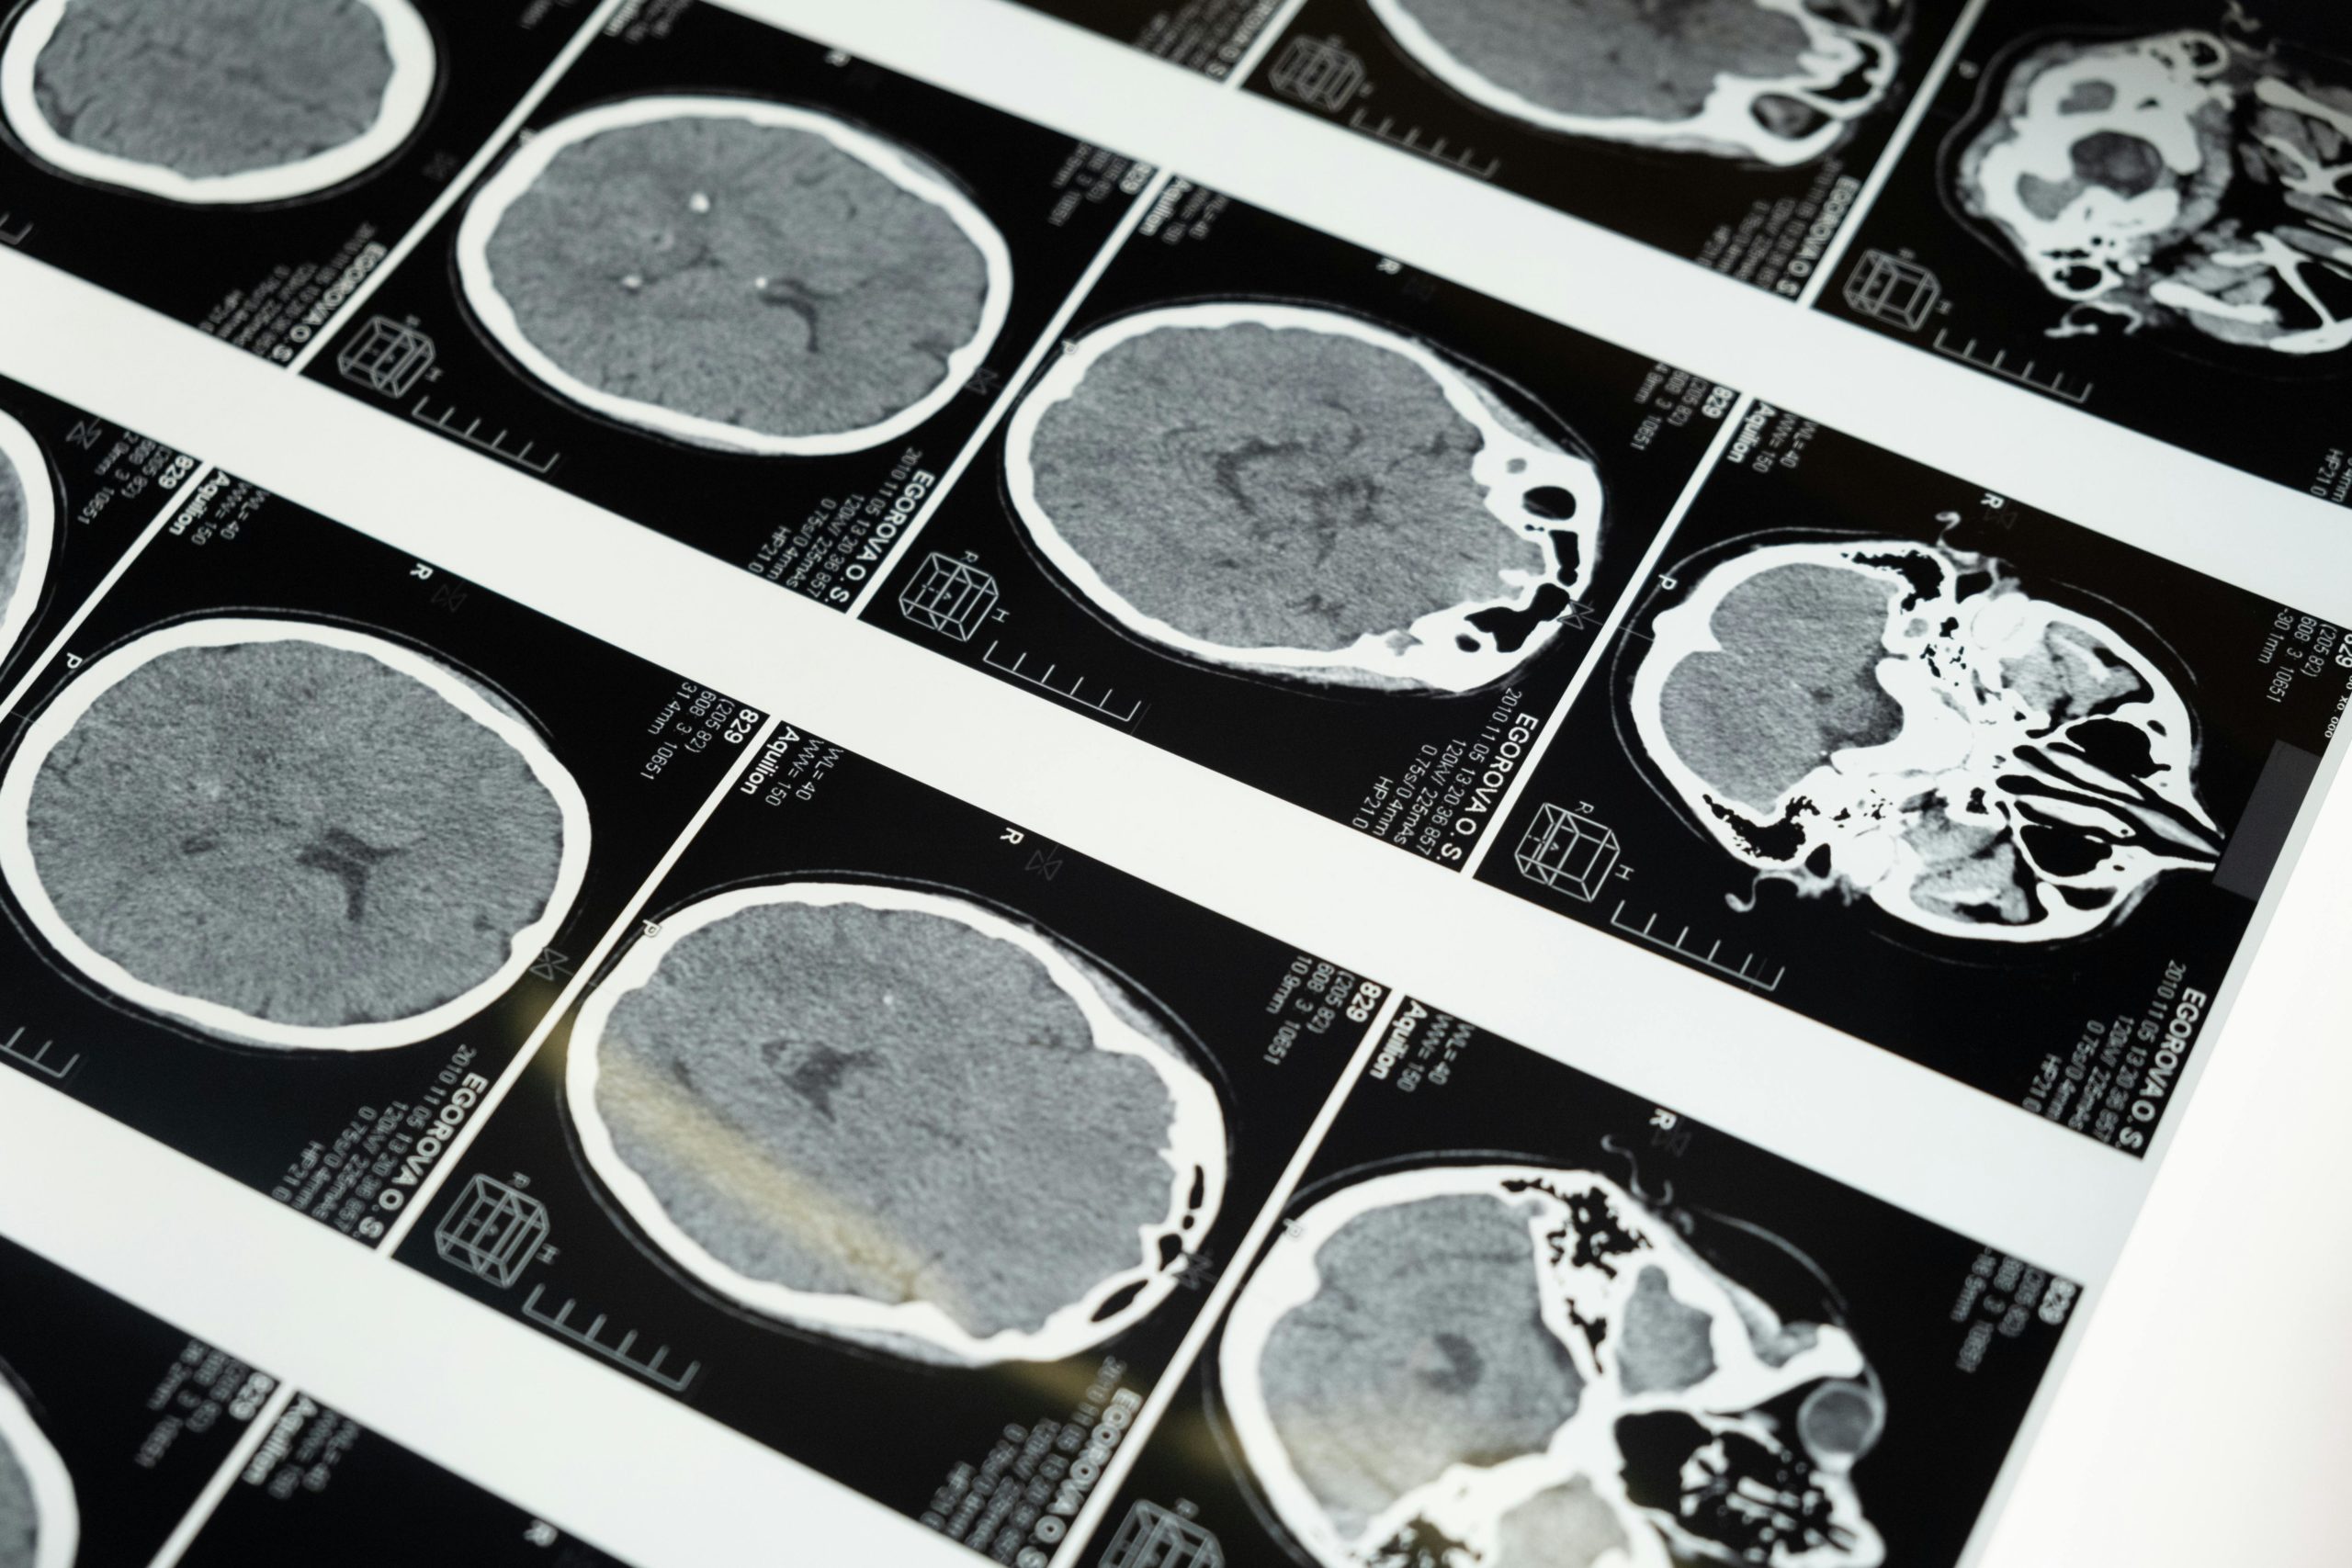

Gehirnforscher nutzen verschiedene Methoden, um im lebenden Menschen Einsicht in die Hirnaktivität zu gewinnen. Die wichtigsten Verfahren sind bildgebende Neuroimaging-Methoden und das EEG.

• MRT (Magnetresonanztomografie): Mit dem MRT können Forscher die Struktur und teilweise auch die Aktivität des Gehirns messen. Normale MRT-Bilder zeigen z. B. das Volumen von Hirnarealen oder bestimmen, ob die Anatomie normal ist. In der Lernforschung verwendet man vor allem das fMRT (funktionelle MRT). Dabei bleibt die Person in einer Röhre liegen und löst Aufgaben, während das Gerät Blutfluss und Sauerstoffverbrauch misst. Aktive Hirnregionen „leuchten“ dadurch in den Bildern auf.

• PET (Positronen-Emissions-Tomografie): Hierfür injiziert man eine schwach radioaktive Substanz, die sich im Blut verteilt und vor allem in besonders aktiven Hirnarealen anreichert. Die Messung zeigt dann eine Art „Karte“ der Gehirnaktivität. Ein Vorteil ist, dass bestimmte Stoffwechselvorgänge sichtbar werden. Allerdings ist PET aufwendiger und kommt seltener in der Lernforschung zum Einsatz.